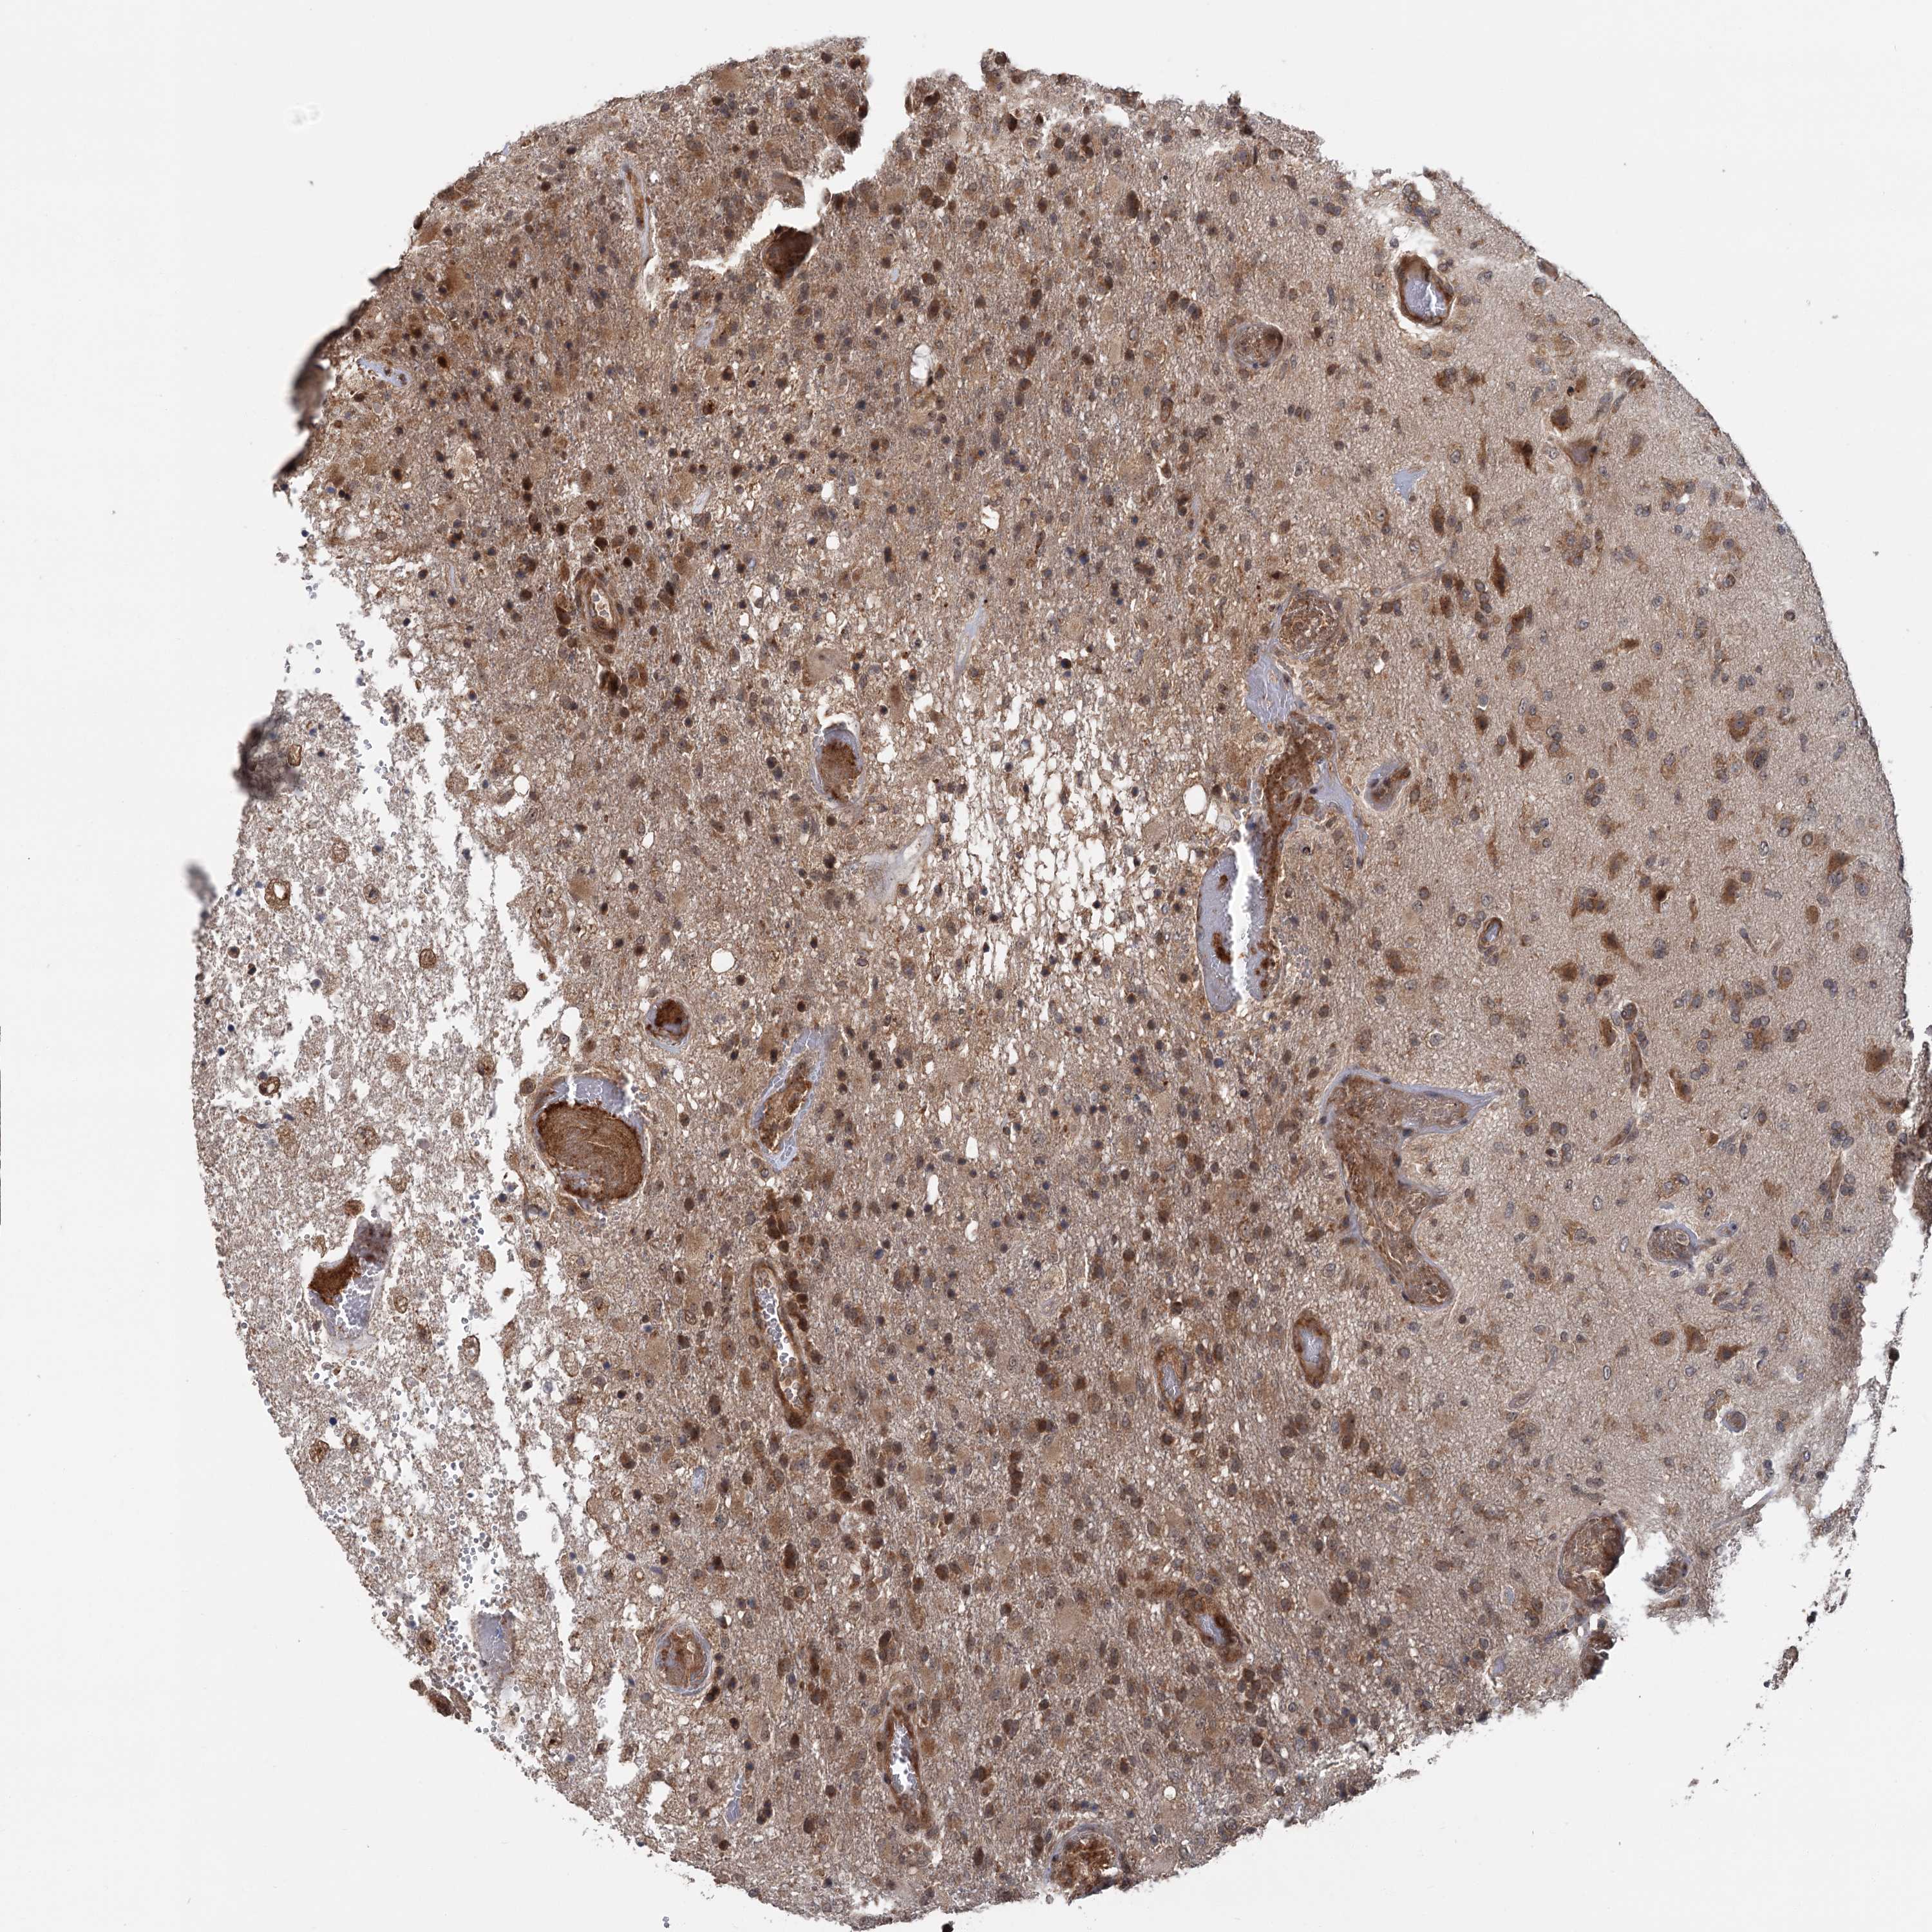

GLIOMA - Protein expressioni

A mouse-over function shows sample information and annotation data. Click on an image to view it in a full screen mode. Samples can be filtered based on level of antibody staining by selecting one or several of the following categories: high, medium, low and not detected. The assay and annotation is described here.

Note that samples used for immunohistochemistry by the Human Protein Atlas do not correspond to samples in the TCGA dataset.

Antibody stainingi

Antibody staining in the annotated cell types in the current human tissue is reported as not detected, low, medium, or high, based on conventional immunohistochemistry profiling in selected tissues. This score is based on the combination of the staining intensity and fraction of stained cells.

Each image is clickable and will lead to virtual microscopy that enables deeper exploration of all samples and also displays staining intensity scores, fraction scores and subcellular localization as well as patient and tissue information for each sample.

Antibody HPA038497

Antibody HPA038498

Staining

High

Medium

Low

Not detected

Intensity

Strong

Moderate

Weak

Negative

Quantity

>75%

75%-25%

<25%

None

Location

Nuclear

Cytoplasmic/membranous

Cytoplasmic/membranous,nuclear

Glioma, malignant, High grade

Glioma, malignant, Low grade